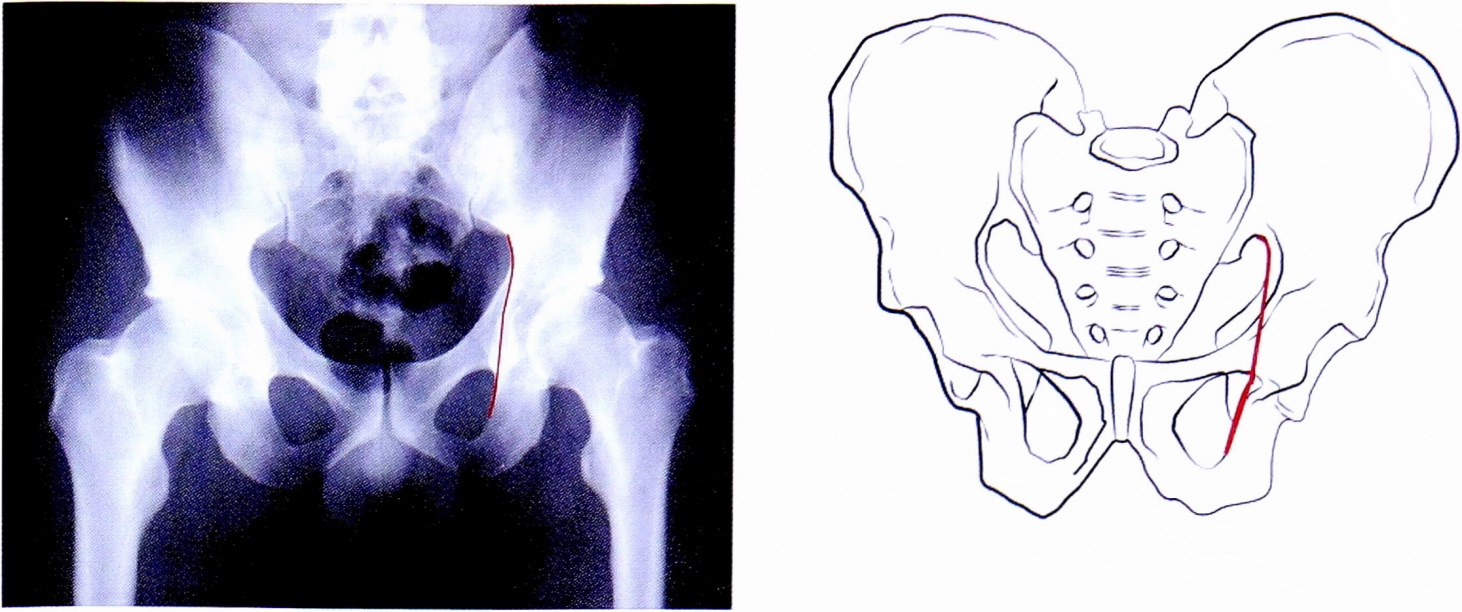

Таким образом, методом исключения неповрежденных структур вертлужной впадины, диагностирован перелом задней колонны вертлужной впадины. Повреждение подвздошно-седалищной линии и деформация контуров запирательного отверстия подтверждает этот диагноз (рис. 28). На рентгенограмме в косой запирательной проекции определяется задний вывих головки бедренной кости и отсутствие отдельного фрагмента задней стенки (рис. 29).

Рис. 28. Верификация перелома задней колонны.

Fig. 28. Verification of posterior column fracture.

Рис. 29. Рентгенограмма в косой запирательной проекции.

Fig. 29. Obturetor oblique view.